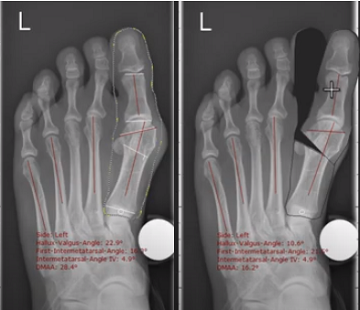

+ Đo đạc đối với bệnh lý Hallux valgus (Tình trạng vẹo ngoài của ngón cái)

Phân tích tình hình trước phẫu thuật thông qua tính toán tự động tất cả các góc độ liên quan.